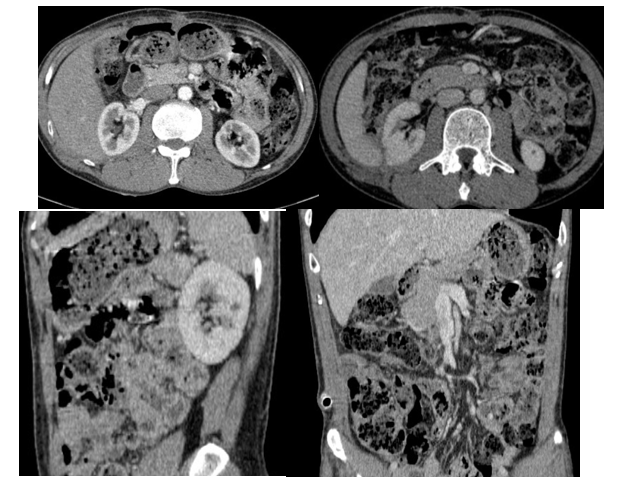

- CTscanner ổ bụng: Phát triển từ khoang sau phúc mạc bên phải có khối lớn kích thước khoảng 253x127mm, tỷ trọng hỗn hợp gồm phần đặc ngấm thuốc sau tiêm, thành phần nang dịch, mỡ và các ổ tăng tỷ trọng tự nhiên trước tiêm dạng máu cục lớn nhất kích thước khoảng 83x64 mm theo dõi liposarcoma. Khối lớn đẩy thận phải ra trước, sang trái sát đường giữa, đẩy nhu mô gan lên trên và đẩy các quai ruột trong ổ bụng sang trái. Không ghi nhận tổn thương ở các cơ quan khác.

Hình 2. Hình ảnh chụp cắt lớp vi tính ổ bụng: Khối khoang sau phúc mạc – Theo dõi Liposarcoma (vòng tròn màu đỏ)